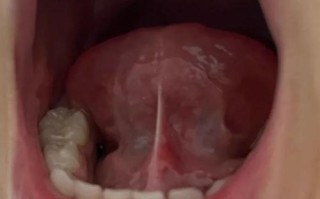

儿童健康 儿童舌系带短手术费用是多少? 影响费用的主要因素手术方式(最关键的因素)门诊小手术(最常见,费用较低):方法:在口腔科门诊进行,医生使用专业的剪刀或激光刀,在局部麻醉下快速完成剪开,整个过程通常只需几分钟到十几分钟,费用构成:通常... 99ANYc3cd6 2025-11-27 0 #儿童舌系带短手术费用 #舌系带短手术价格多少 #小儿舌系带矫正费用